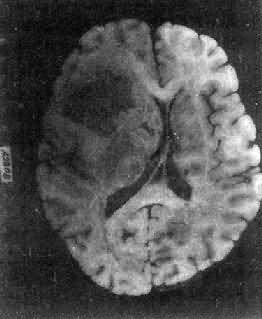

肉眼观,肿呈球形,分叶状或不规则形,质实或硬,边界清楚,周围脑组织受压成凹陷切迹(图16-27)。少数肿呈斑块状覆盖较广泛区域,甚至整个脑半球,称为斑块型脑膜。肿质地硬,切面灰白色,呈颗粒状、条索旋涡状,有的质地似砂砾样,乃由于有多量砂粒体存在。

图16-27 脑膜

于大脑两半球间有一近似球形肿,边界清楚,周围脑组织受压萎缩